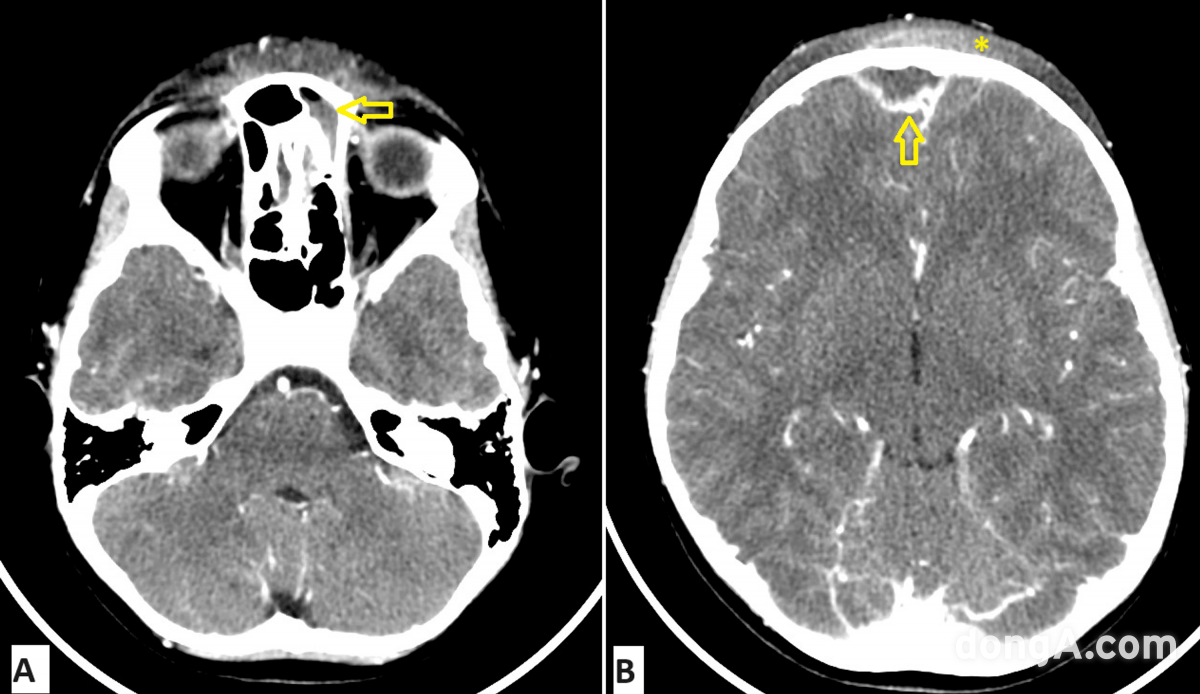

사진=Cureus 5월 호 캡처.

사진=Cureus 5월 호 캡처.단순한 코막힘으로 여겼던 증상이 8살 남자아이의 이마를 불룩하게 만들며 의료진에게 충격을 안겼다. 진단 결과는 두개골 감염성 질환이었다.

CT 검사 결과, 급성 전두동염(이마 부위 축농증)이 두개골과 그 주변으로 퍼졌다는 사실이 밝혀졌다.

의료진은 뇌와 가까운 부위까지 감염이 퍼지는 희귀 질환인 ‘팟츠 퍼피 종양(Pott’s Puffy Tumor)’을 진단했다.

아이에게는 이마 뼈 속에 고름이 고인 ‘골수염’과 ‘피하 고름집’, ‘두피 염증’까지 나타났다.